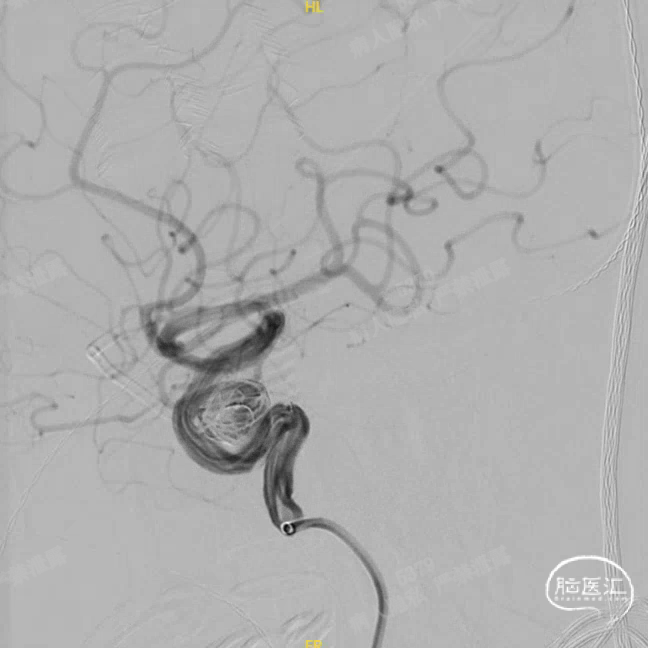

术中DSA造影:右侧颈内动脉工作角度及3D造影,显示右侧颈内动脉海绵窦段动脉瘤。

微导管超选入动脉瘤腔内,通过微导管使用弹簧圈填塞动脉瘤腔。

Headway™ 27 156cm微导管内输送FRED 5514血流导向密网支架,系统远端精准定位于预计着陆区以远2-3mm,回撤微导管原位释放支架,头端锚定在颈内眼动脉段。继续原位释放支架,注意保证微导管头端在释放过程中位于血管中央。

正位

①输送导丝头端

②支架远端显影点

③工作段螺旋显影丝

④支架近端显影点

完全释放FRED 5514血流导向密网支架,正、侧位造影及术后CT复查结果观察,载瘤动脉通畅、支架贴壁良好、动脉瘤内造影剂滞留、颅内未见明显异常。